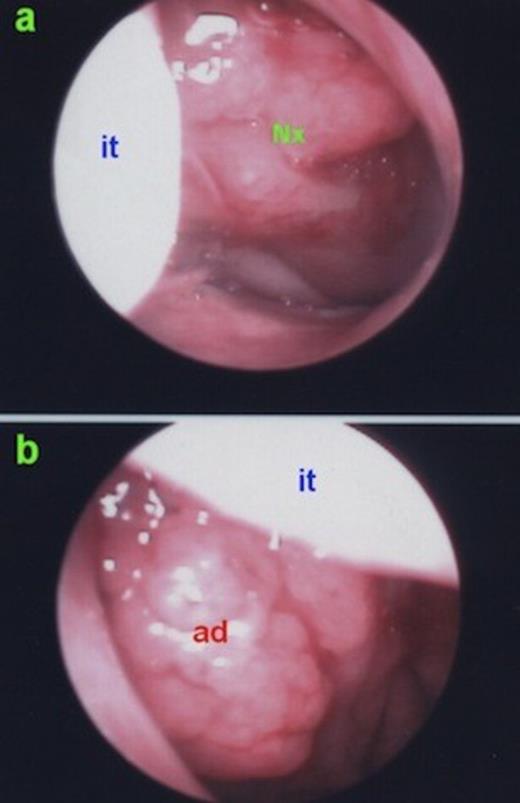

The patient underwent endonasal endoscopic surgery with the diagnosis of rhinolithiasis. The rhinolith was successfully removed with minimal possible injury to surrounding nasal mucosa. The nasal cavity was irrigated with saline. After removal of the rhinolith, adenoid hypertrophy was prominent on the left side (Figure 3). Adenoidectomy was subsequently performed and postoperative histopathologic examination revealed lymphoid hyperplasia and chronic inflammatory cell infiltration without any malignant transformation.

a) Right nasal cavity; clinically insignificant lymphoid hyperplasia on the nasopharynx. b) Left nasal cavity; clinically significant adenoid hypertrophy. it: inferior turbinate, ad: adenoid hypertrophy, Nx: Nasopharynx.